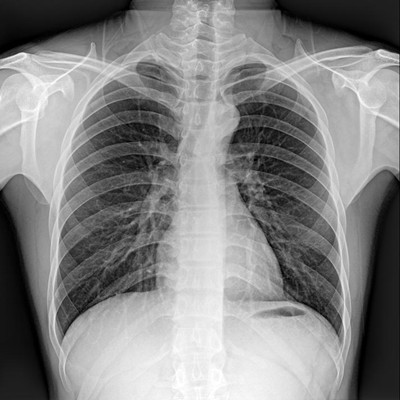

●探測器可以大范圍轉(zhuǎn)動,大尺寸有效探測面積,可滿足人體多部位攝影需求。